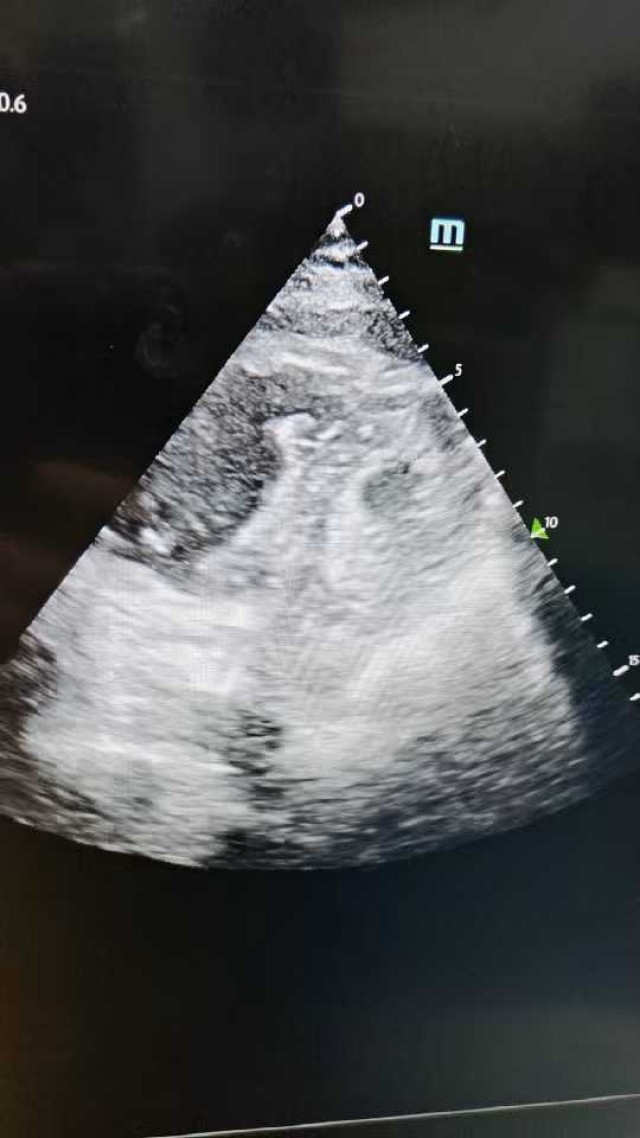

反思 | 赶高铁时一过性晕厥的老年男性

昨天值班遇到的一例晕厥病例,差点漏诊,而最终的解法,始于最简单而质朴的查体。国庆中秋双节的最后一天,8号的早上8点,抢救室床旁晨交班,病人依旧是多而重,交到6床,一个刚入室不久的病人,准备去做CT,夜班医师汇报病史:69岁男性,本次因“头晕伴一过性晕厥1小时”为主诉入抢,1小时前于高铁站因即将赶不上高铁走路快时突发头晕,伴一过性晕厥,约3-4分钟后清醒,清醒后诉今晨未吃早餐,已服用降压药物,仍有头晕头痛、四肢乏力等不适,无胸闷胸痛,无畏寒发热,无咳嗽咳痰,无恶心呕吐,无肢体麻木,无视物模糊等不适,路人拨打120送至我院急诊就诊。既往高血压,长期服用氨氯地平+福辛普利,血压控制一般;糖尿病,长期